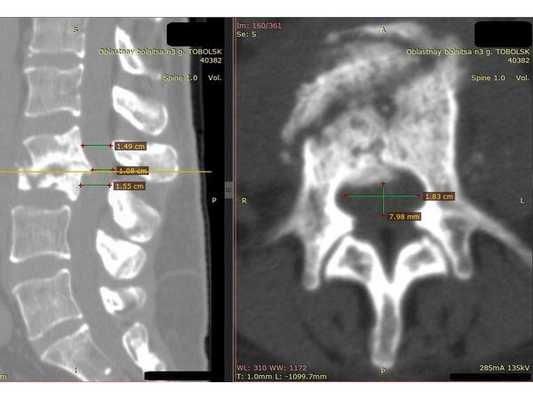

Функциональная спондилография поясничного отдела от 12.02.2019: остеохондроз II степени; спондилоартроз; нестабильность сегментов на уровне L4-L5 и L5-S1; ретролистез — смещение L5 позвонка назад — I степени. Электронейромиография (ЭНМГ) от 12.02.2019: малоберцовые нервы в норме с обеих сторон; признаки заинтересованности корешков L4-S1 справа. Мультиспиральная компьютерная томография (МСКТ) ПКОП от 13.02.2019: КТ-картина дегенеративно-дистрофических изменений поясничного отдела позвоночника; большая задняя срединная грыжа межпозвонкового диска на уровне L4-L5 позвонков с абсолютным стенозом спинального канала; задние диффузные протрузии дисков L5-S1 и умеренная протрузия уровня L2-L3. МРТ ПКОП от 14.02.2019: МР-картина дегенеративно-дистрофических изменений сегментов ПКОП; задняя медианная экструзия (выбухание) диска L4-L5 с признаками компрессии корешков конского хвоста и вторичного дурального стеноза на уровне L4-L5 на 2/3; протрузии дисков L2-L3 и L5-S1; ретролистез L5 I степени.

КТ пояснично-крестцового отдела позвоночника показала состояние после перенесённого спондилодисцита L2-L3 (воспалительного заболевания инфекционного характера) с разрушением тела L3 позвонка и кифотической деформацией (искривлением позвоночника) на данном уровне.

Состояние после перенесённого спондилодисцита L2, L3 позвонков с формированием абсолютного стеноза (критического сужения просвета в позвоночном столбе) на уровне L2-L3 и развитием нижнего парапареза